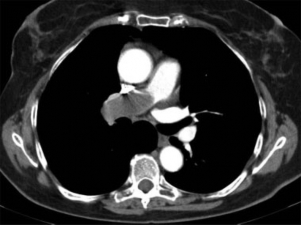

Presentamos el caso de una mujer de 72 años con antecedentes de carcinoma ductal infiltrante de mama en remisión seis años antes, que acudió a urgencias por dolor torácico, disnea y tos seca persistente. Tenía una angiografía coronaria reciente normal y los análisis de laboratorio revelaron como valor destacable un dímero-D de 742 µg/l. Con esos datos se solicitó desde el servicio de urgencias una angio-TC de arterias pulmonares (►Fig. 1) donde se apreciaba un voluminoso defecto de repleción en la arteria pulmonar derecha que se diagnosticó como TEP. La paciente fue anticoagulada y controlada con mejoría inicial, pero cuatro meses después volvió a urgencias con empeoramiento de la disnea, tos y hemoptisis. En las radiografías de tórax (►Fig. 2) se apreciaba un aumento de tamaño de arterias pulmonares con una masa parahiliar izquierda y atelectasia completa de lóbulo superior izquierdo (LSI), mejor valorados en la angio-TC torácica (►Fig. 3), donde persistía la ocupación arterial con unas características que, unidas a su evolución, sugirieron un origen tumoral. Se realizó biopsia a través de broncoscopia de la masa que obstruía el bronquio del lóbulo superior izquierdo, con un resultado histológico de sarcoma intimal de arterias pulmonares (►Fig. 4), patología muy poco frecuente y de difícil diagnóstico diferencial con el TEP.

Angio-tomografía computada (TC) de arterias pulmonares donde se observa un voluminoso defecto de repleción que ocupa totalmente la luz de la arteria principal derecha con incremento del calibre del vaso. En el contexto clínico propuesto se sugirió el diagnóstico de tromboembolismo pulmonar.